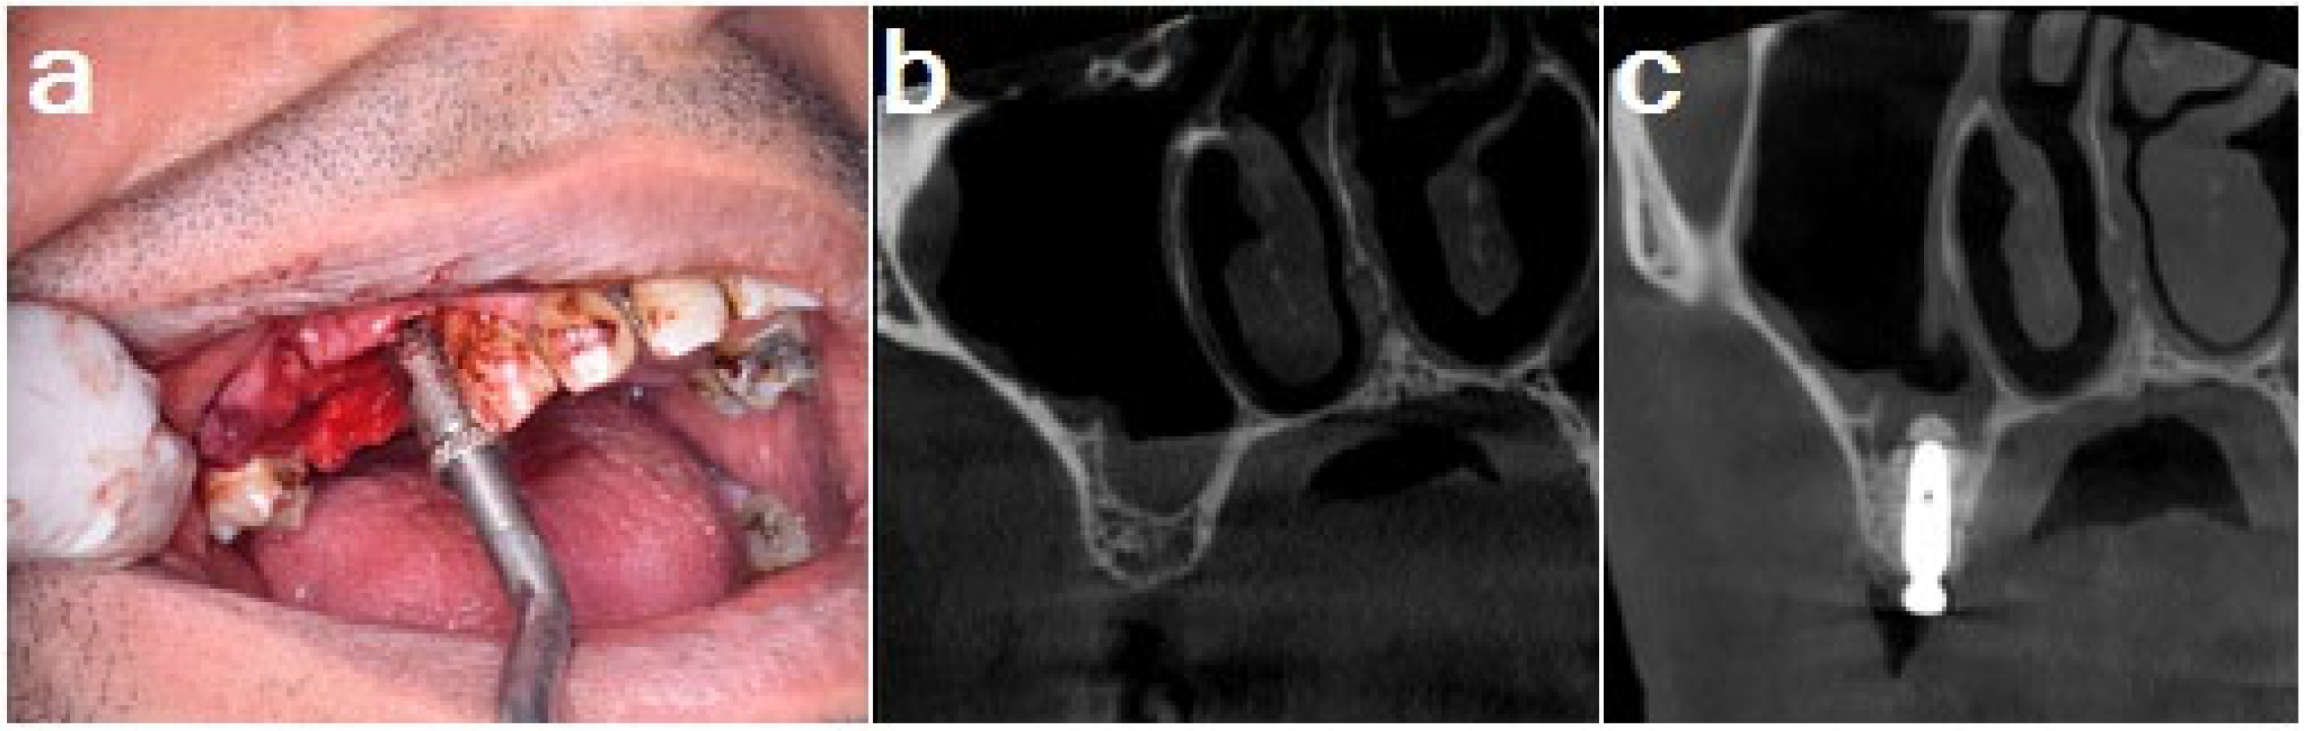

Group 3: Osteotome sinus lift: The drills were used sequentially (3.0 and 3.5 mm) to increase the size of the osteotomy site to the same level (1 mm away from the sinus floor). An osteotome with a diameter of 4 mm, slightly smaller than the planned implant fixture, was placed in the prepared implant site, tapped gently to reach the same level, and then lightly tapped to break up the sinus floor (Figure 3).

Figure 3. (a) Osteotome sinus floor elevation, (b) CBCT preoperative cross-section and (c) CBCT cross-section of implant showing the sinus floor elevation after 6 months.